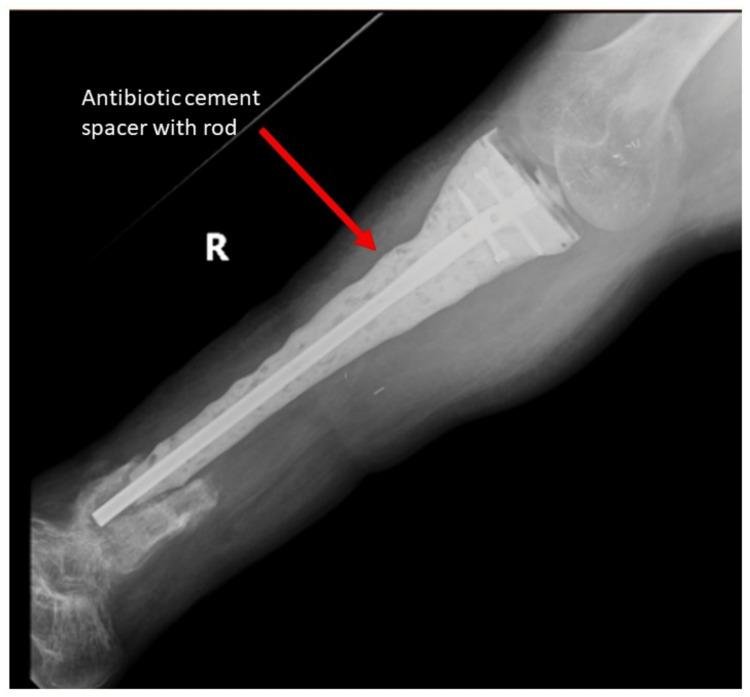

Ollier's disease is a rare syndrome characterized by multiple enchondromas with the potential for malignant transformation. The treatment for secondary chondrosarcoma is surgical resection, which can be a morbid procedure depending on the location and size of the tumor. We present a successful limb salvage in which the majority of the tibia was removed and replaced with a megaprosthesis. The complex reconstruction in this case required the use of a novel uncemented stem.

骨软骨瘤病是一种罕见的综合征,其特征为多发性内生软骨瘤并有恶变的可能。继发性软骨肉瘤的治疗方法是手术切除,根据肿瘤的位置和大小,这可能是一个创伤性较大的手术。我们展示了一例成功的保肢手术,其中大部分胫骨被切除并用一个大型假体进行了置换。该病例中的复杂重建需要使用一种新型的非骨水泥型柄。